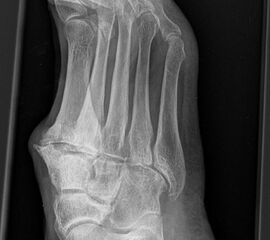

Eine Röntgenaufnahme unter Belastung mit Abbildungen des ganzen Fußes a. p. (mit 15-20° Röhrenkippung) und seitlich, sowie Schrägaufnahmen, reichen meist zur Diagnose. Manchmal ist ein MRT und DVT ergänzend hilfreich. Selten wird die Indikation für ein SPECT CT gestellt (Abb. 6).

• konventionelle Röntgenbilder mit Belastung im Stehen a. p. und seitlich, ggf. schräg (Abb. 9, 10 und 11).

• Röntgenkontrolle nach 8-10 Wochen, dann - je nach knöchernem Durchbau - Übergang zur Vollbelastung im Konfektionsschuh (Abb. 24 und 25).